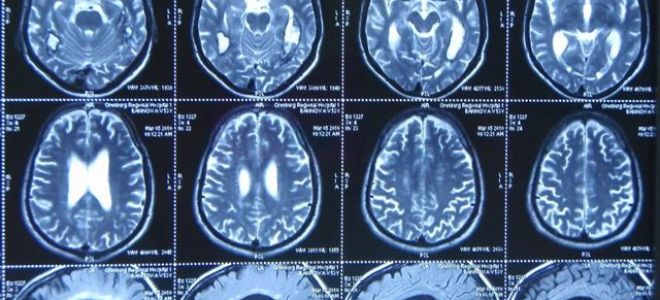

Ээг или мрт головного мозга: отличие, что лучше?

Что такое энцефалограмма головного мозга?